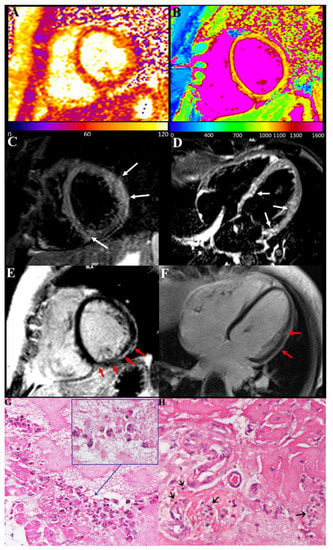

CMR showed in our three patients a diffuse increase in both T2 and T1 myocardial value, as a result of diffuse inflammatory involvement (Figure 2 and Figure 3). LGE was present as well and patchily distributed in the subepicardial myocardium. Severe compromise of LV contractility of 35 and 28% was registered in pt2 (Figure 3) and pt3, respectively.

Endomyocardial biopsy findings were characterized in all three cases by the presence of inflammatory infiltrates, mainly represented by degranulated eosinophils and to a very less amount of lymphocytes (Figure 2) focally associated with necrosis of the adjacent myocytes. In a sample from a pt1 manifesting junctional rhythm and no atrial activity at electrophysiological study, peripheral sections of conduction tissue (Purkinje fibers) were included, being infiltrated and damaged by eosinophils (Figure 2).

Figure 2. Eosinophilic myocarditis with conduction tissue involvement after COVID-19 mRNA vaccination. (A,B): Myocardial T2 (A) and T1 (B) maps, acquired on mid-ventricular short-axis view, showed a diffuse increase in both T2 and T1 myocardial value as a result of a diffuse inflammatory involvement. (C,D): Presence of myocardial edema was also confirmed on STIR T2-weighted images acquired on short-axis (C) and horizontal long-axis (D) views as multiple areas of hyperintense signal within the basal septum, the inferior interventricular junction and mid-basal anterolateral wall (arrows). (E,F): Late-enhancement images acquired on the same short-axis (E) and horizontal long-axis (F) planes reveal tiny areas of mild enhancement with “patchy” distribution and predominant involvement of subepicardial layer in the same location of the above-mentioned myocardial edema (red arrows). (G,H): Histology shows degranulation of crystalloids of eosinophilic granulocytes (see insert and blue arrow) responsible for the release of the cationic protein and ultimately for myocardial damage and a strongly infiltration of eosinophils in the conduction tissue (H) (black arrow). (400× magnification).